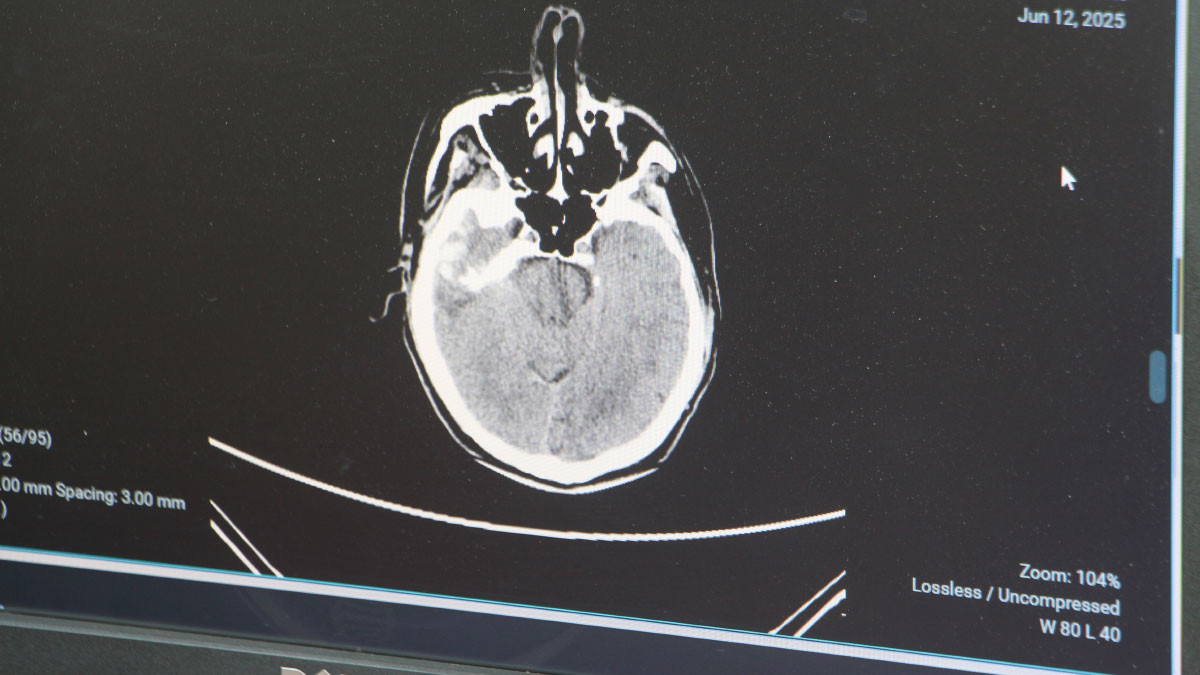

Genellikle 50 yaştan sonra görülen beyin kanaması, son yıllarda gençlerde daha sık görülmeye başlandı. Sebeplerine dikkati çeken Adana Şehir Hastanesi Beyin ve Sinir Cerrahisi Bölümü'nden Doç. Dr. Ali İhsan Ökten, bunların daha çok "arteriyovenöz malformasyon" ve "anevrizma" kaynaklı yaşandığını söyledi.

Anevrizma, yani kan damarlarının duvarında oluşan baloncuk şeklindeki patolojik genişlemeler kaynaklı yaşanan beyin kanamalarının 100 binde 10 ile 15 kişi arasında görüldüğünü dile getiren Doç. Dr. Ali İhsan Ökten, "Gençlerde görülme oranı giderek artıyor" dedi.